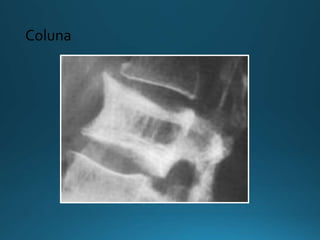

• Espessamento cortical nas margens do corpo

vertebral (“vértebra em moldura”)

• Trabeculado grosseiro na direção vertical

(mais grosseiro que nos hemangiomas)

• Achatamento da margem anterior do corpo

vertebral (vértebra quadrada)

Imagem - Rx

Fase mista

Coluna

• Espessamento corticalnas margens do corpo vertebral (“vértebra em moldura”) • Trabeculado grosseiro na direção vertical (mais grosseiro que nos hemangiomas) • Achatamento da margem anterior do corpo vertebral (vértebra quadrada) Imagem - Rx Fase mista

• Pode acometerapenas um, alguns ou todos os níveis • Esclerose difusa do corpo vertebral (“vértebra em marfim”) • Elementos posteriores também podem ser afetados • Aumento da vértebra com ou sem os elementos posteriores Imagem - Rx Fase blástica